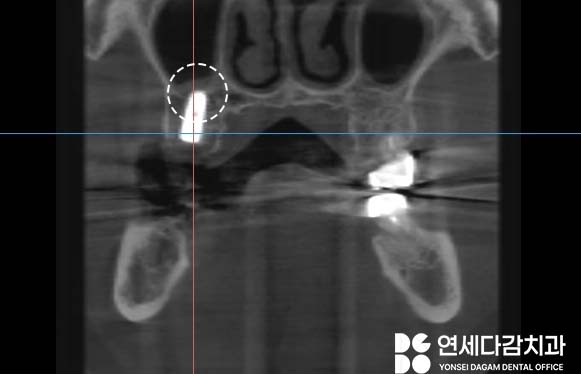

골밀도가 전반적으로 낮다는

점을 고려하여,

상악동 저부에 위치한 피질골을

적극 활용하는 전략을 수립했습니다.

피질골은 뼈의 외측에 위치하여

단단하고 치밀한 뼈조직으로,

해면골에 비해

우수한 고정력을 제공할 수 있습니다.

이와 동시에 일반적으로 사용되는

길이보다 더 긴 고정체를 선택하여,

근단부(끝부분)가 상악동 저의

피질골에 닿도록 시행했습니다.

이를 통해 상악동 저의

단단한 피질골에서 고정력을

얻을 수 있었습니다.

상악동저 피질골을 활용한

접근법이 잘 적용됐음을

확인할 수 있었습니다.